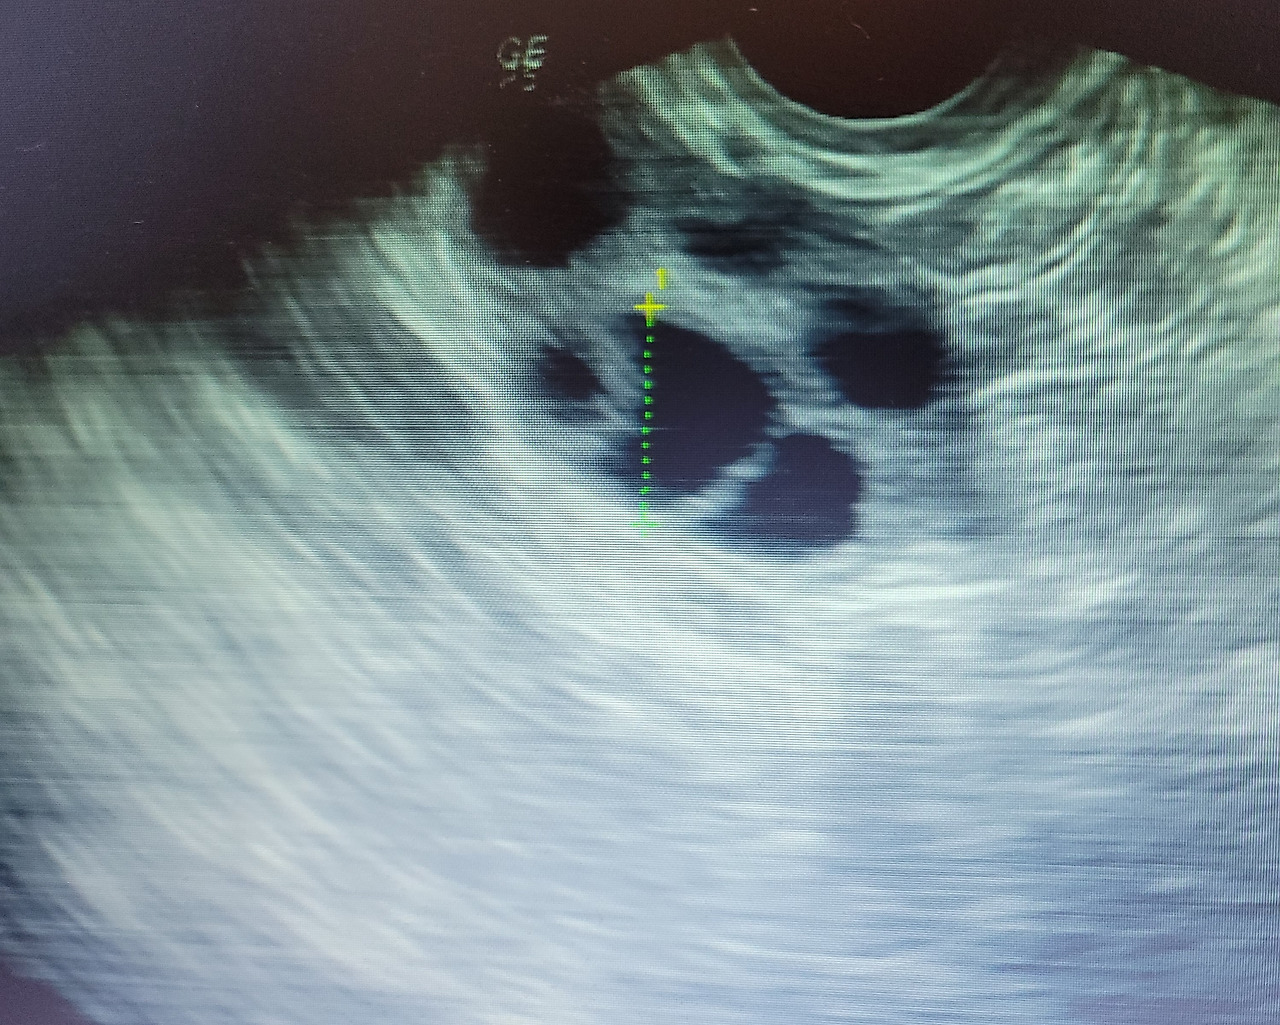

3일 전에는 여러 난포 중에서도 1개가 유독 컸는데

오늘은 비슷비슷하게 커 보였다.

저번에는 동그란 모양이 다 보였으면,

이번에는 몸집이 커졌다고 서로 겹쳐 보였다.

동그란 거품이 여럿 뭉치면 각이 생겨 보이는 거처럼 말이다.

16은 돼야 하는데, 13 정도니까....

지금 한 10개쯤 크고 있고,

3~5개가 될 거 같은데.....